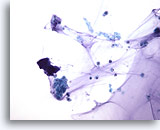

Lavage du bassinet, négatif

Les lavages avec 50 ml de solution saline avant la manipulation de la vessie donnent généralement des échantillons riches en cellules.

20x

Lavage du bassinet, négatif

Les lavages avec 50 ml de solution saline avant la manipulation de la vessie donnent généralement des échantillons riches en cellules.

20x